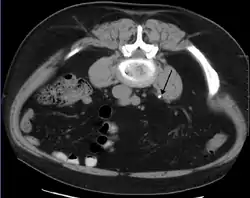

In people with a history of stones, those who are less than 50 years of age and are presenting with the symptoms of stones without any concerning signs do not require helical CT scan imaging.[49] A CT scan is also not typically recommended in children.[50]

Otherwise a noncontrast helical CT scan with 5 millimeters (0.2 in) sections is the diagnostic method to use to detect kidney stones and confirm the diagnosis of kidney stone disease.[13][47][51][52][7] Near all stones are detectable on CT scans with the exception of those composed of certain drug residues in the urine,[53] such as from indinavir. Calcium-containing stones are relatively radiodense, and they can often be detected by a traditional radiograph of the abdomen that includes the kidneys, ureters, and bladder (KUB film).[53] Some 60% of all renal stones are radiopaque.[51][54] In general, calcium phosphate stones have the greatest density, followed by calcium oxalate and magnesium ammonium phosphate stones. Cystine calculi are only faintly radiodense, while uric acid stones are usually entirely radiolucent.[55]